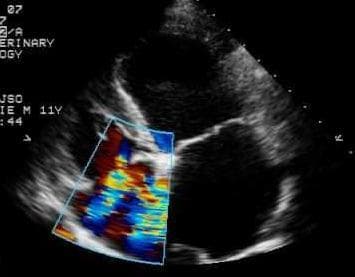

ЭХО сердца (эхокардиография, ЭХОКГ, УЗИ сердца) — это исследование сердца с помощью импульсного ультразвука, позволяющее оценить структуру, размеры и состояние сердечных мышц и клапанов. Данный метод исследования основан на регистрации ультразвуковых волн, отраженных от различных структур органа и кровеносных сосудов.

Применение ЭХО сердца дает возможность изучить работу сердца, проследить изменения скорости и особенности движения крови в предсердиях и желудочках, что имеет очень важное диагностическое значение при выявлении патологических состояний сердечно-сосудистой системы.

Исследование позволяет увидеть объемное изображение органа, сделать виртуальные срезы, оценить размер сердечных структур, объем камер, толщину стенок. С помощью этого метода можно определить массу мышечной ткани сердца и оценить сократительную функцию миокарда.

Данный метод является экспертным в диагностике заболеваний сердечно-сосудистой системы, лечение всего спектра кардио-патологий по современным стандартам невозможно без рутинного применения ЭХОкардиографии и доплерографии. В нашем ветеринарном центре выполняются как скриннинговые ЭХОКГ, направленные на ранее выявление заболеваний с бессимптомным течением, так и диагностические, в рамках приема ветеринарного врача-кардиолога.